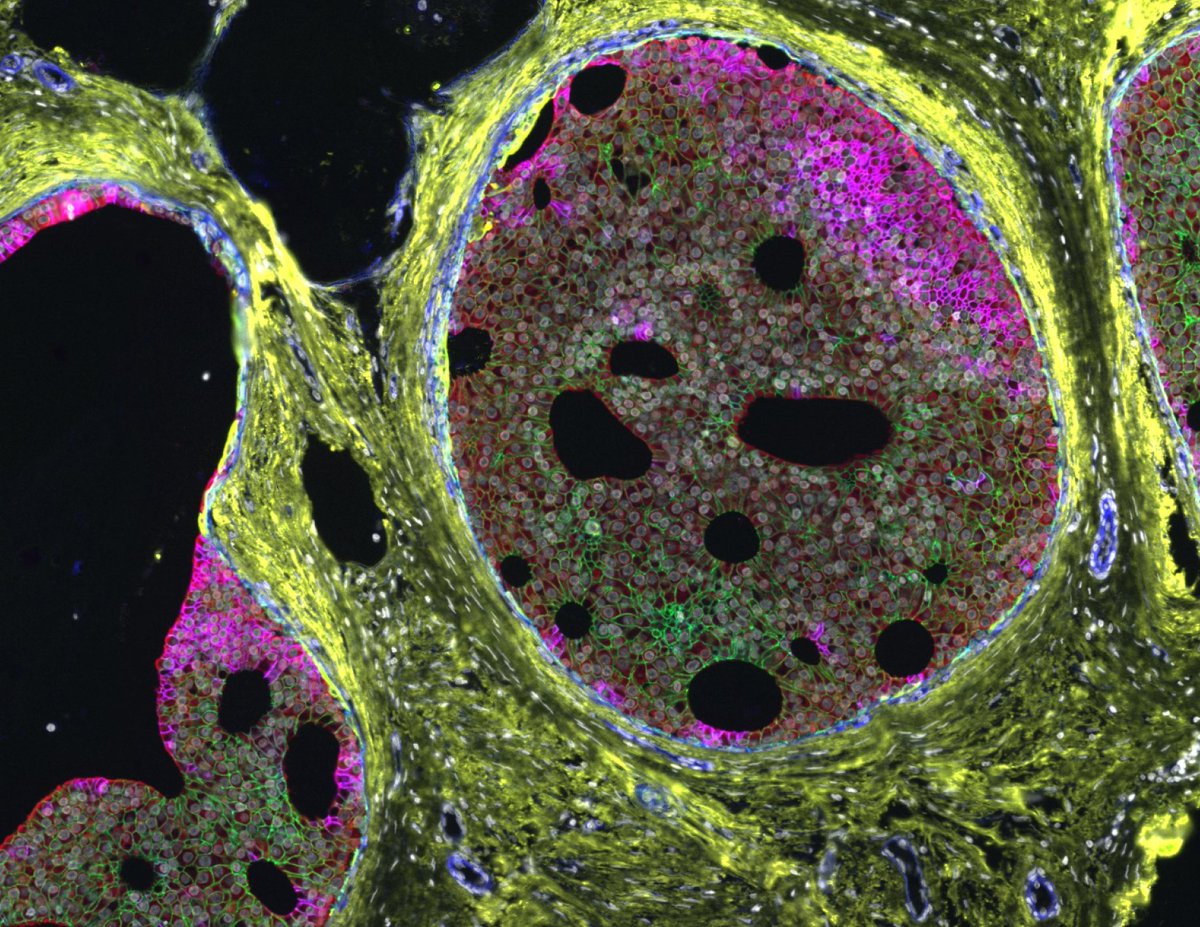

Successful Orion training at @UBC. 🚀 The Poh Lab is using the Orion spatial proteomics platform to map the tumor immune microenvironment in oral cancer.